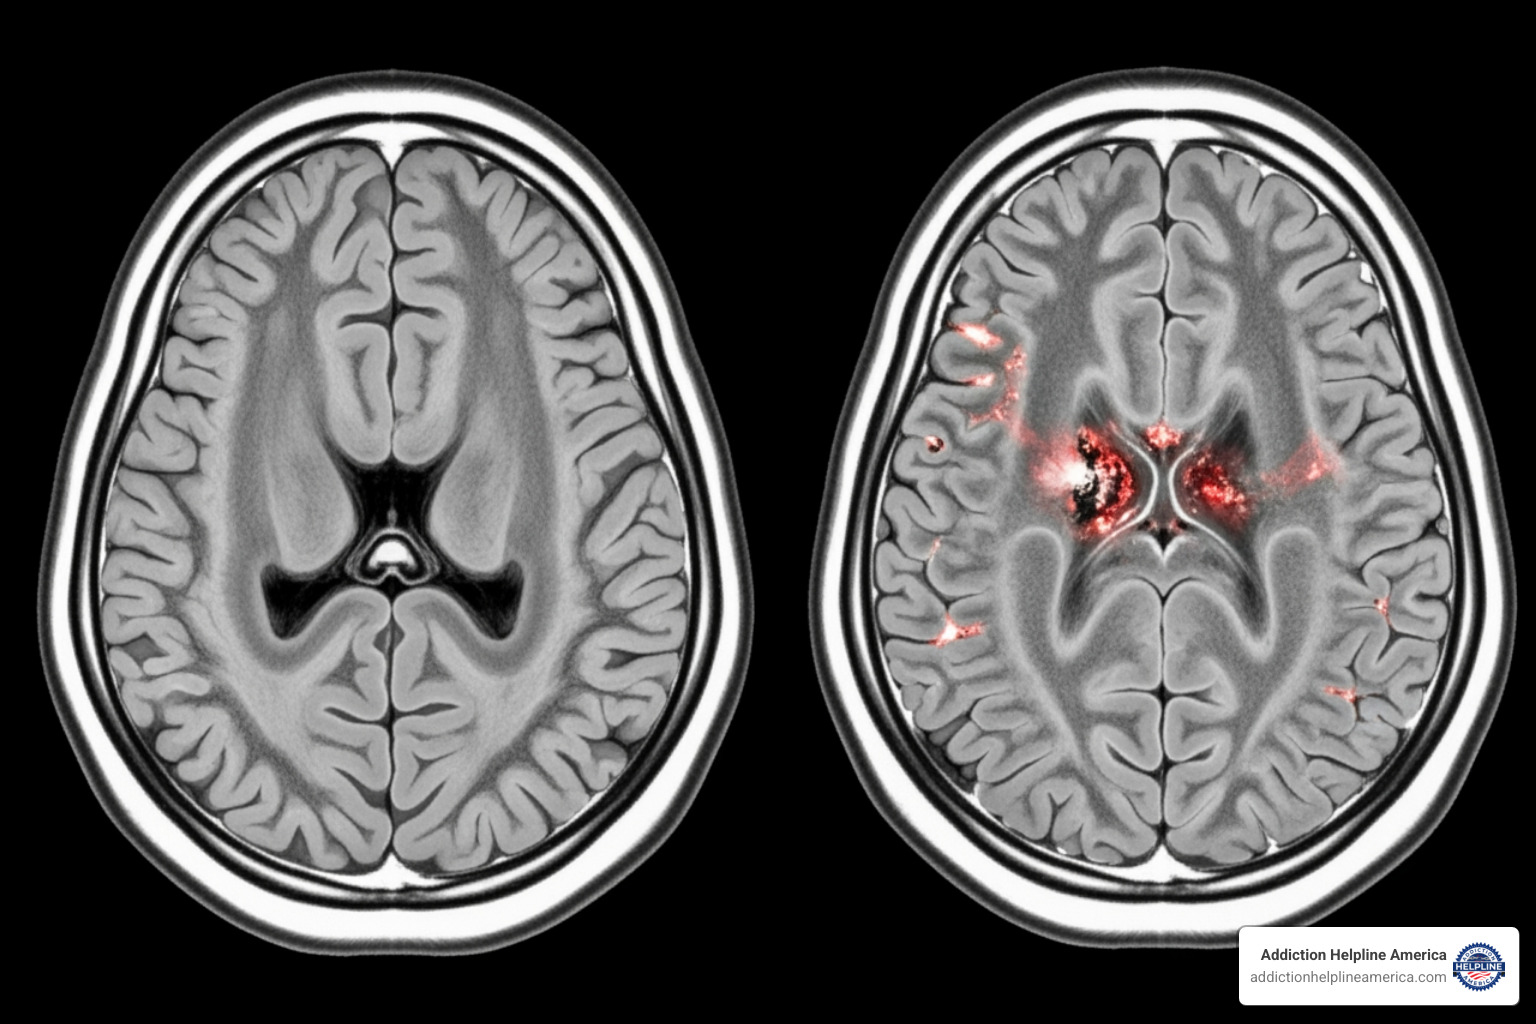

Drugs hijack the brain’s reward system, flooding it with dopamine at levels far beyond natural pleasures. The brain is tricked into prioritizing the drug above all else for survival. Over time, the brain adapts by becoming less sensitive to dopamine. Natural joys no longer feel rewarding, and the person needs the drug just to feel normal. This is why people on drugs often lose interest in activities they once loved.

Addiction also weakens the prefrontal cortex, the brain’s center for judgment and self-control. The brain is rewired to crave the drug while the ability to resist that craving is damaged. This is why telling someone to “just stop” is ineffective; it ignores the profound neurological changes that have occurred.